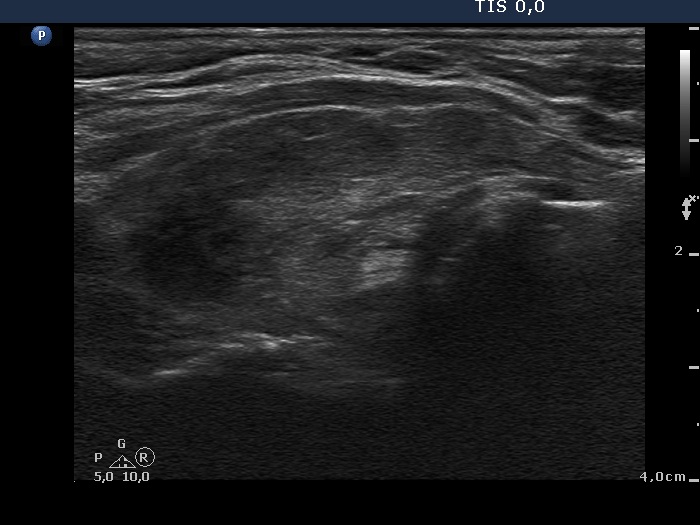

Fourth examination 21 months after initial investigation (fourth and fifth rows):

Clinical presentation: The patient requested a second opinion. Multiple nodules including a suspicious one in the right lobe were described in another institute. Scintigraphy diagnosed multiple "cold" and warm" nodules in both lobes. Surgery was advised. The surgeon asked aspiration cytology of the hypoechogenic nodule described as suspicious on ultrasonography.

Palpation: unchanged.

Results of blood tests: euthyroidism on daily 25 mg methimazole (TSH 3.78 mIU/L, FT4 10.9 pM/L).

Ultrasonography: unchanged.Cytology was performed from the hypoechogenic area in the upper part of the right thyroid.

Cytological diagnosis: benign pattern corresponding to previous dysfunction and isotope therapy.

The patient underwent total thyroidectomy. Histopathology disclosed diffuse goiter corresponding to Graves' disease and focal lymphocytic thyroiditis. There were no nodules.

Comment. It is worth analyzing the echo pattern of the thyroid. The small hypoechogenic area in the right lobe changed neither in size nor is shape nor in vascularization over 11 months.